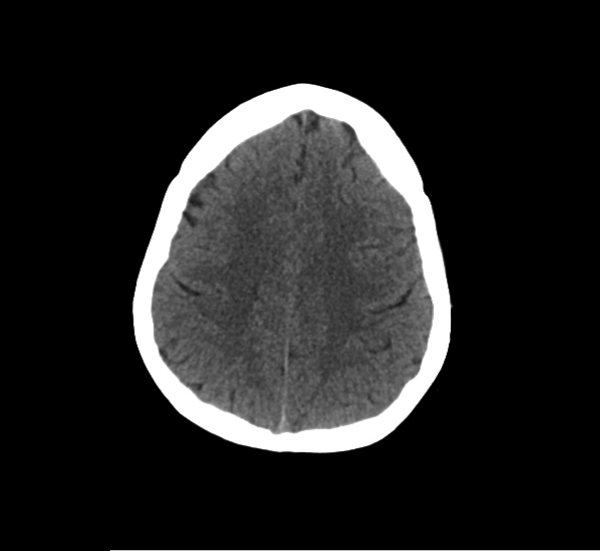

CT Brain Anatomy